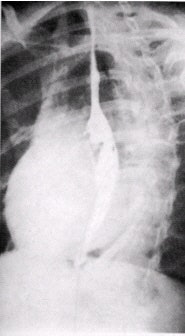

| Left anterior oblique projection, single-contrast esophagram. Image courtesy of Dr. Naveed Ahmad. |

- Place the patient in the right anterior oblique (RAO) position to offset the esophagus from the spine. The patient’s right arm is placed alongside the body, with the left knee flexed.

- The technologist should place the cup of barium in the patient’s left hand, with the straw between the patient’s teeth.

- The patient’s neck is turned to the left, and the head is placed flat on a pillow. Patients who are unable to tolerate this position may be imaged in the left posterior oblique (LPO) position.

- Position the fluoroscope so that the apex of the left lung appears at the top of the monitor.

- The technologist will ask the patient to continuously drink the barium. This fills and distends the esophagus while the technologist obtains images of the proximal esophagus, midesophagus, and the distal esophagus, including an open lower esophageal sphincter (magnified if possible).